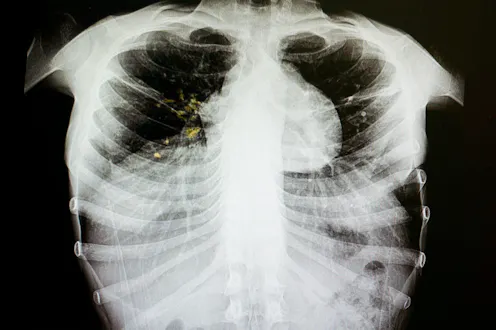

Tuberculosis (TB) is one of the leading causes of death from infectious diseases. Globally, it accounts for around 1.3 million deaths and 10.4 million people develop the disease every year.